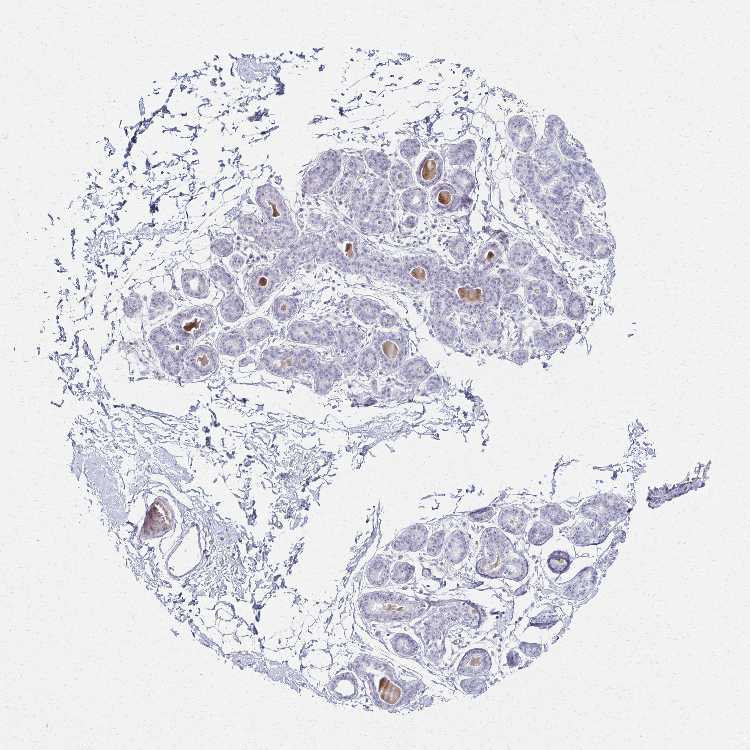

BREAST - Antibody stainingi

Antibody staining in the annotated cell types in the current human tissue is reported as not detected, low, medium, or high, based on conventional immunohistochemistry profiling in selected tissues. This score is based on the combination of the staining intensity and fraction of stained cells.

Each image is clickable and will lead to virtual microscopy that enables deeper exploration of all samples and also displays staining intensity scores, fraction scores and subcellular localization as well as patient and tissue information for each sample.

Antibody HPA061223

Adipocytes Not detected

Glandular cells Not detected

Myoepithelial cells Not detected